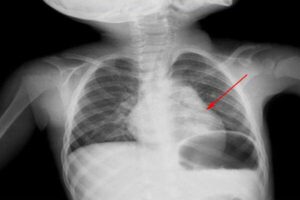

Особенности пневмонии у детей 1, 2 и 3 лет

Пневмония часто развивается после длительной простуды или неадекватного лечения, но может развиваться и сама по себе. В этой статье мы подробно рассмотрим пневмонию у детей 1-3 лет, ее особенности, симптомы и лечение. Особенности по возрастам Наиболее подвержены развитию пневмонии маленькие дети. Это связано с тем, что иммунная система растущего организма еще не сформирована, дыхательные мышцы …